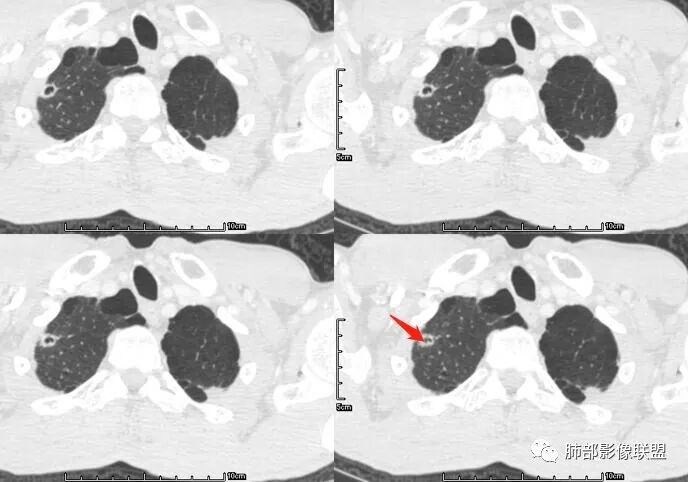

张延军:双肺多发结节,空洞影,后者洞壁厚薄不均匀,部分腔内丝丝落落,呈分叶征,边缘见毛刺影,病灶大部分位于胸膜下,与血管相连,右肺下叶前基底段结节近段支气管截断,远端见空腔。左肺下叶病灶密度不均,背段支气管壁增厚,管腔狭窄。考虑1.双肺下叶占位性病变伴肺内空洞性转移 2.多原发的占位 3.肉芽肿性血管炎代排。

生来征服~浪子:@吴婧南京市第一医院 结节和血管多相连续,空洞内不干净。结核这样的还是少吧,是不是放后点,吴老师。

@毛勤香 柳州龙潭医院影像  转移结节很多都有毛刺,有收缩力,而且叶间裂多个结节(符合黄勇老师六个核桃理论)

脐凹征、粗短毛刺、深分叶、中央结构杂乱

本病例左肺下叶肿块,有深分叶、毛刺、胸膜牵拉凹陷、支气管截断及纵隔内淋巴结肿大等征象,都均支持病灶为恶性,如腺癌,而且叶间裂的多发结节也提示是腺癌来源可能大;双肺多发结节、肿块,大部分病灶有分叶、毛刺及胸膜凹陷的恶性征象,与原发肿瘤本身的性质有关,所以应该与左肺下叶肿块同源,而且双肺多发病灶内空洞也具有多样性;

此病例中空洞形态多样,内壁不光整,有分隔影,周围未见明显卫星灶及钙化灶,结核不太符合;患者病史慢性病史,无明显发热,缺乏中毒临床表现,急性感染基本排除;各种中性粒细胞胞浆抗体阴性,没有鼻窦炎,肾脏等病史,基本排除血管炎;霉菌性空洞常见于免疫机能低下者, 常为空洞、肺炎、伴“ 晕圈”征的结节及支气管扩张合并存在。